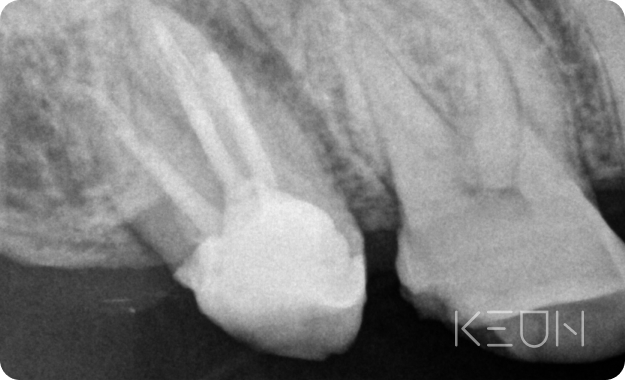

- Before

- After

신경 재치료

신경치료 근관의 개수, 길이, 굵기 등을 측정한 후 치수를 제거하고 근관을 세척해 미세한 근관까지 소독한 후 근관 충전을 하는 방식으로 치료합니다. 그러나 치료 후에도 지속해서 통증이 남아있다면 신경재치료가 필요합니다.